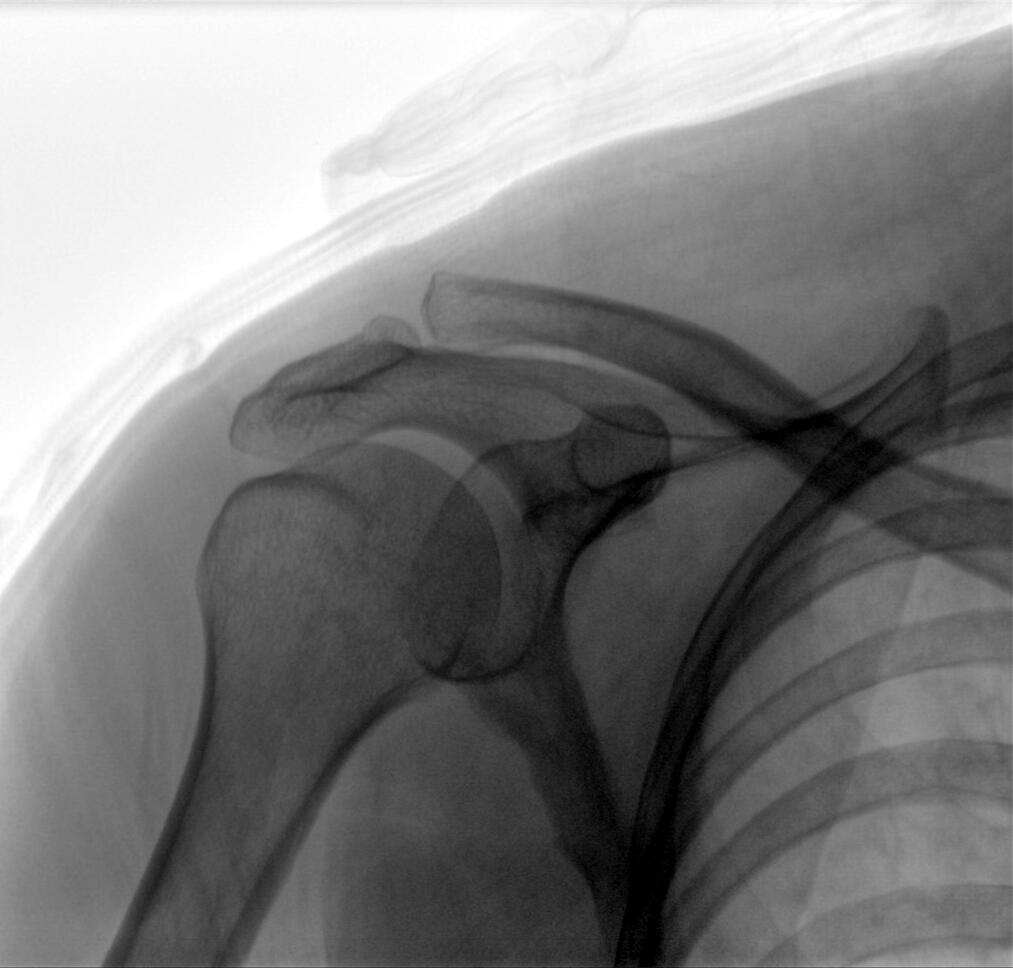

配備了兩種平板尺寸,大尺寸動(dòng)態(tài)平板探測(cè)器成像面積較傳統(tǒng)平板探測(cè)器提升了25%以上,在視野需求大的手術(shù)中,便于醫(yī)生更好定位病灶點(diǎn),規(guī)劃手術(shù)方案,減少因視野范圍不足而多次透視、點(diǎn)片造成的不便,不僅提高了手術(shù)效率,也減少了輻射劑量。